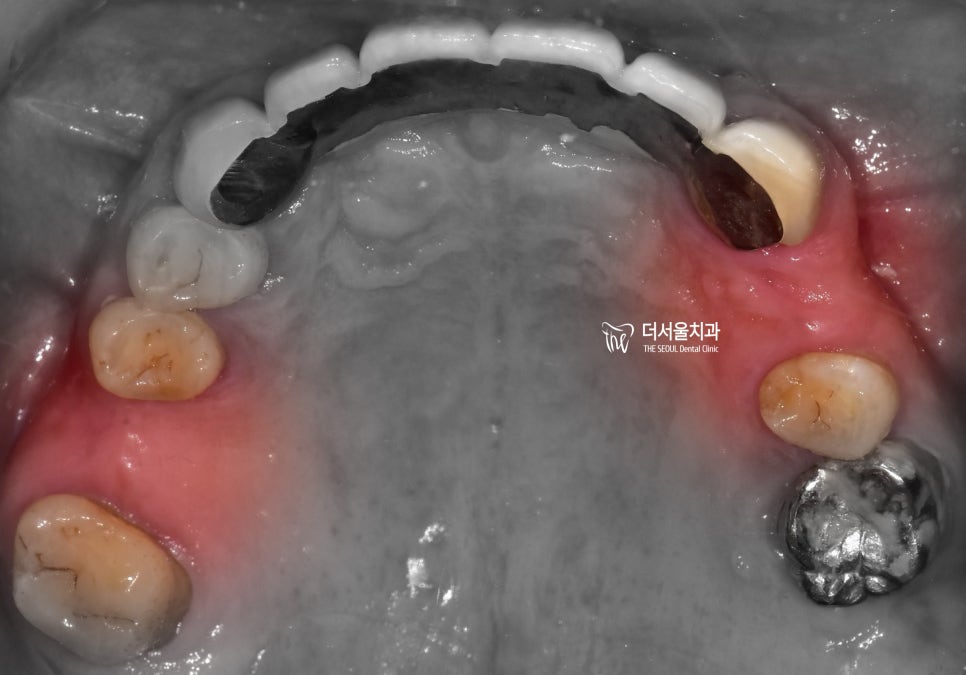

『c.c : 어금니가 없어요.』

상악에는 2곳에서 치아의 결손이 관찰되며

전체 엑스레이로 보게 되면 3곳에서

치아 결손이 관찰 됩니다.

지금 당장 식사를 하는것은 문제가 되지 않지만

이 상태를 그대로 유지를 하게 된다면

추후에는 더 큰 문제가 일어나기 쉬운 상태입니다.

치아 결손 부위에 따라서, 주위에 있는 치아들이

그 빈 틈을 메꾸려 이동을 하게 될 것이고

그에 따라서 결국 교합관계들이 무너지면서

식사를 하는것이 어렵게 되는 상황이

찾아올 수 있게 되는겁니다.